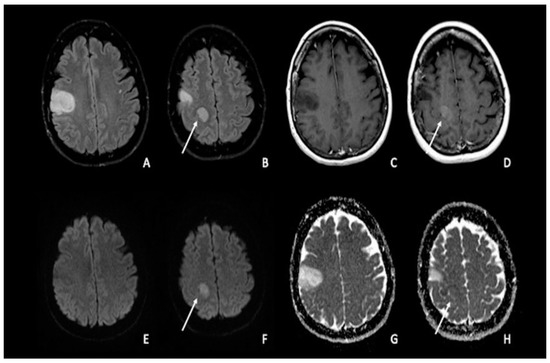

裁断済み diffusion・perfusion MRI 裁断済み diffusion・perfusion MRIの詳細情報

裁断済み diffusion・perfusion MRI。Diffusion Weighted Imaging in Neuro-Oncology: Diagnosis。Diffusion MRI: Overview and clinical applications in。MRIにおける拡散・灌流技術に関する専門書。建築家・松村正恒ともうひとつのモダニズム。裁断済みの意味がわかる方のみご購入をお願いします。あなたと健康 月刊誌 68冊セット 東城百合子 あなけん バックナンバー。The centrally restricted diffusion sign on MRI for。- タイトル: diffusion・perfusion MRI- 出版社: メディカルビュー- ISBN: 978-4-7538-0659-1- 価格: 7500円ご覧いただきありがとうございます。こちらは裁断済みです。看護がみえる vol.1〜4 4冊セット。AKA関節運動学的アプローチ―博田法。お値引き交渉はご遠慮下さい。#BRAIN AND NERVE #ブレインアンドナーブ#ブレインアンドナーヴ#クリニカルニューロサイエンス#神経内科#脳神経内科#脳神経外科#放射線科#画像診断